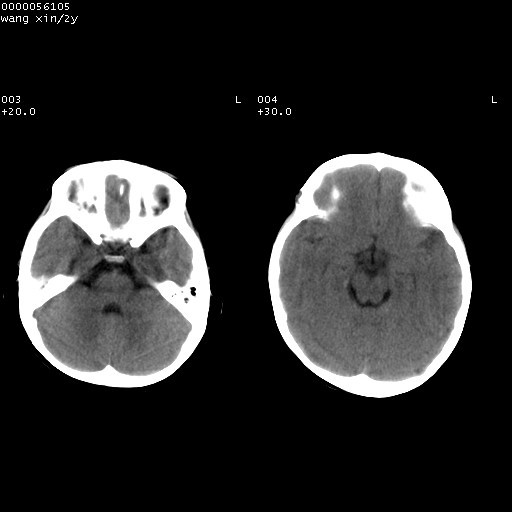

标题: PED1611:F,2Y。右侧额部小包块,光整,质硬,边界清楚,无 [打印本页]

标题: PED1611:F,2Y。右侧额部小包块,光整,质硬,边界清楚,无

右额骨内板压迫性变薄,呈椭圆形膨胀性骨吸收和低密度区,其间可见小斑片状致密影,-支持表皮样囊肿